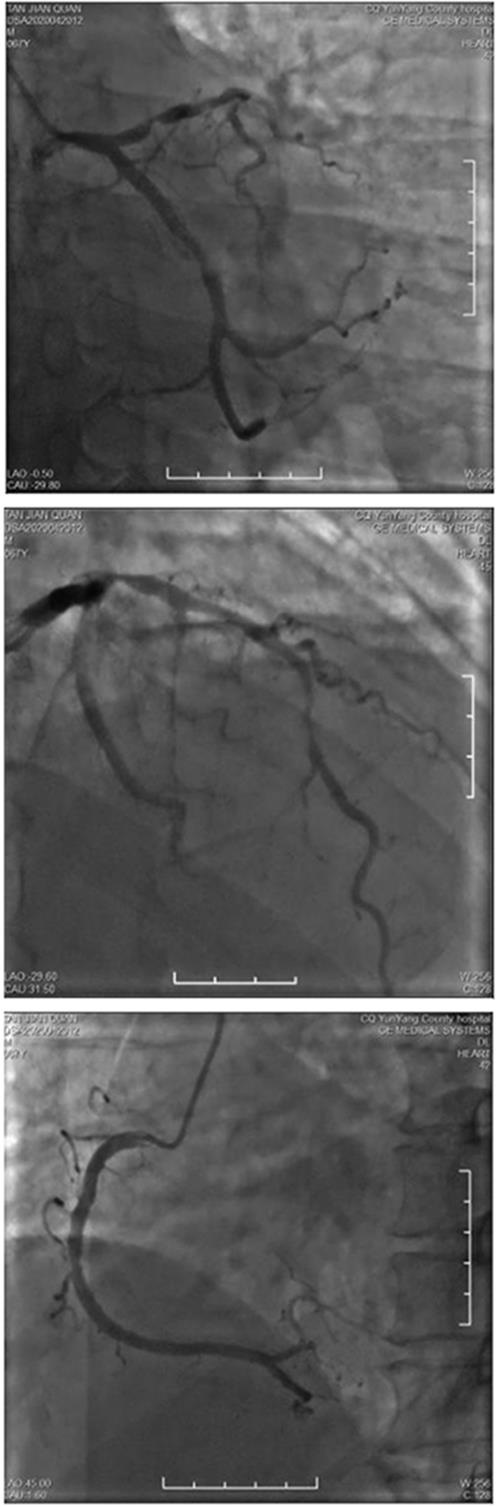

• 疑似雷帕霉素药物洗脱支架术后Kounis综合征1例

2024, 49(1):97-100. DOI: 10.13406/j.cnki.cyxb.003409

摘要 (42) HTML (15) PDF 1.14 M (104) 评论 (0) 收藏

摘要: